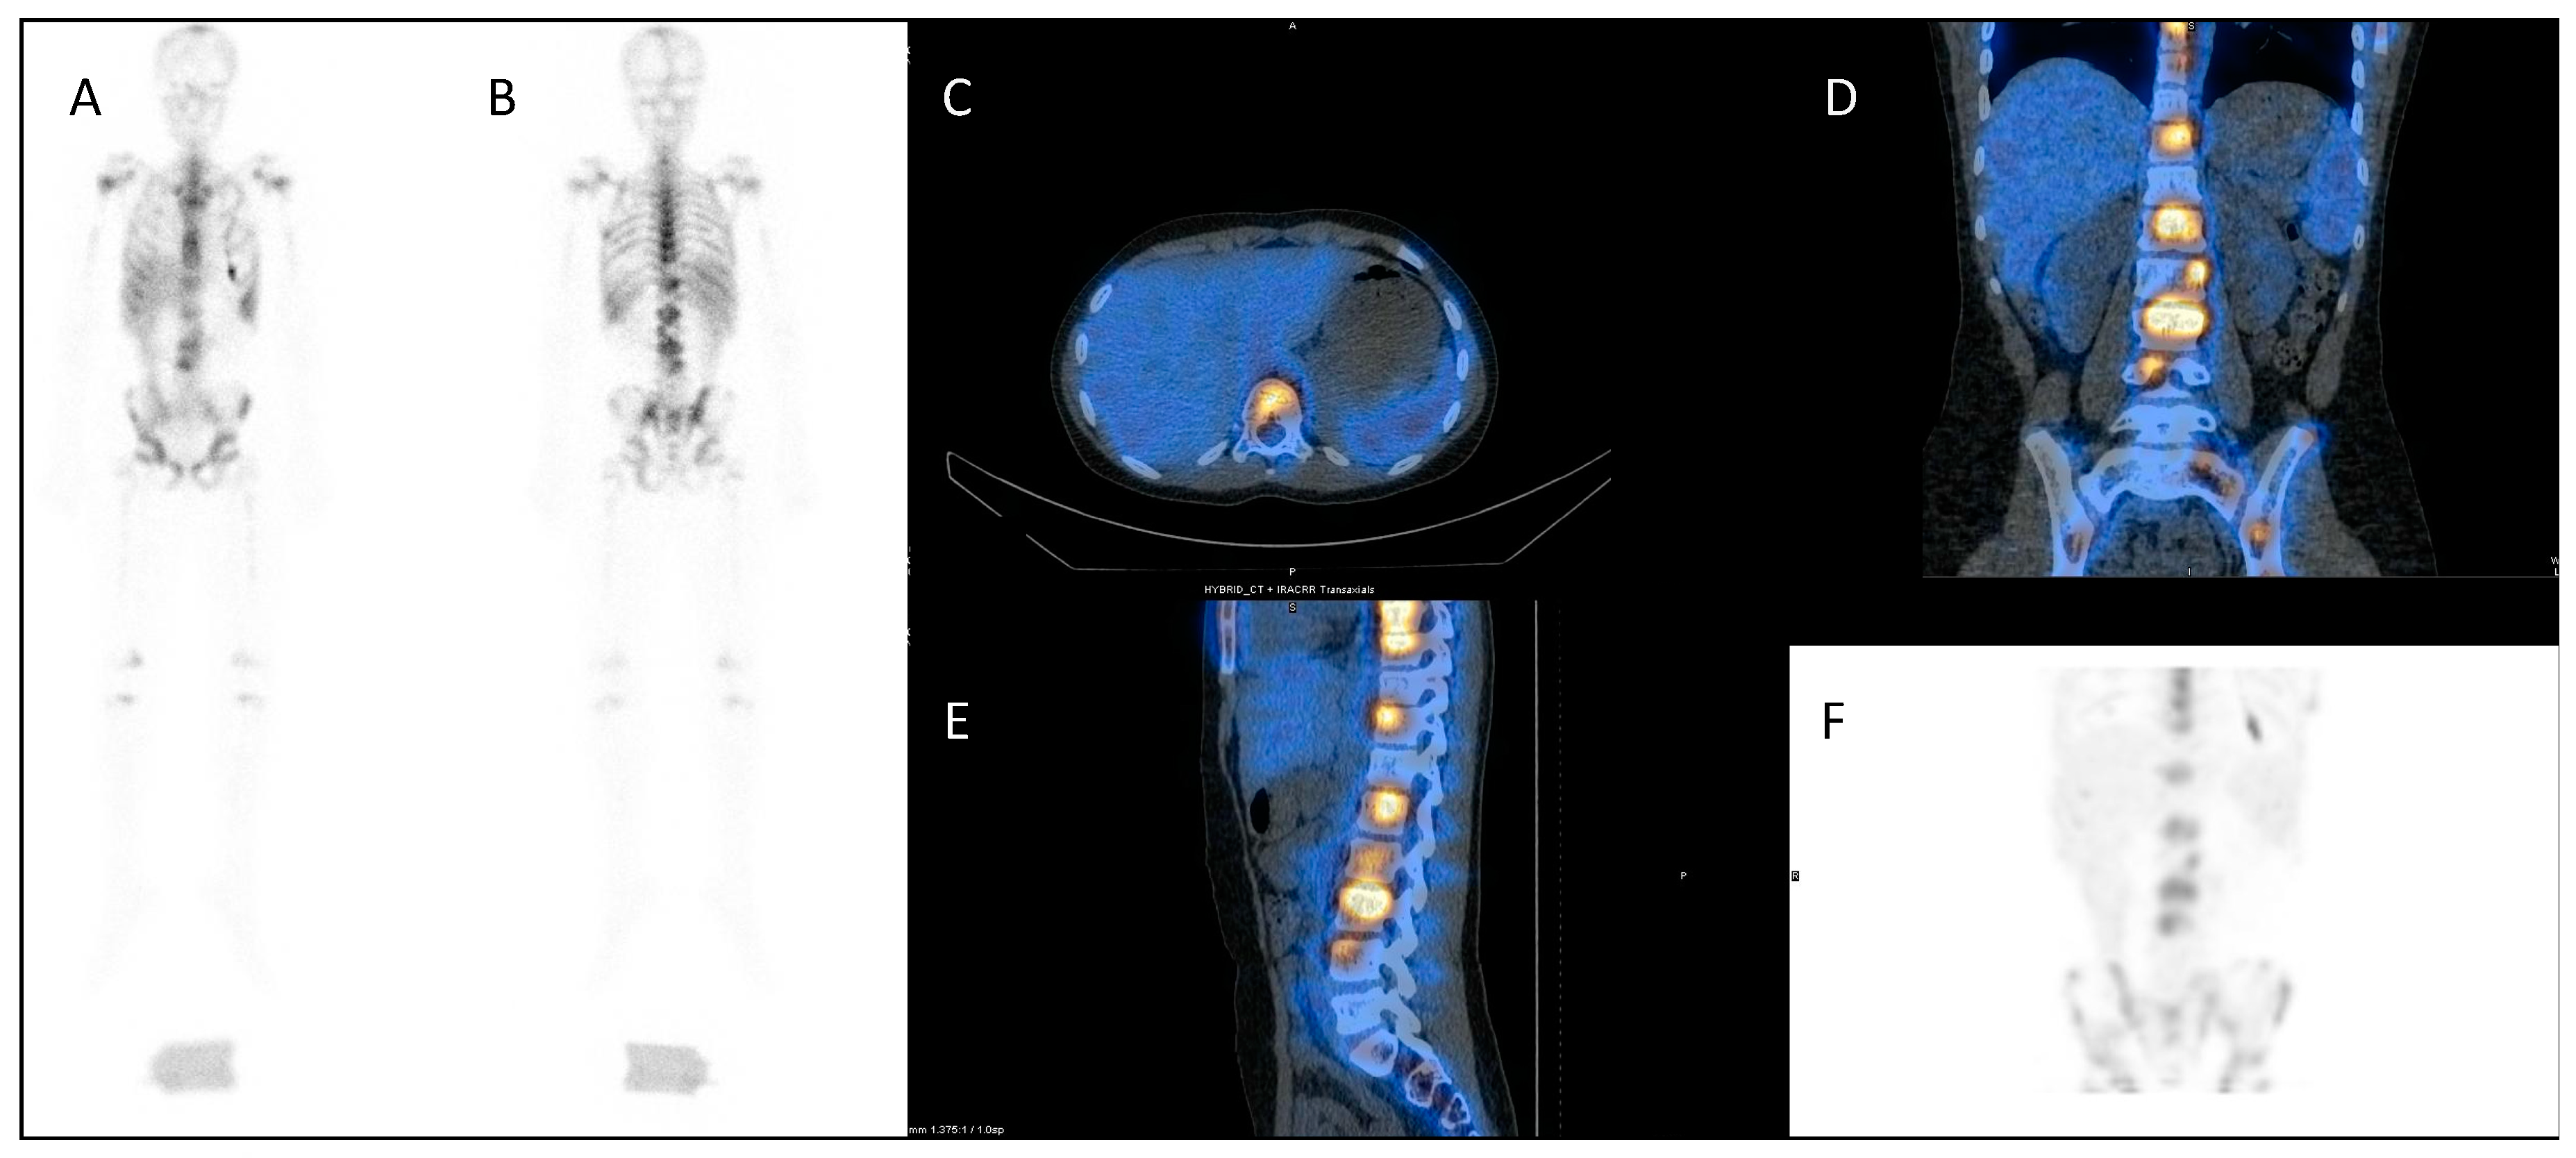

A similar approach is used with serial 111In-labelled anti-CD66 monoclonal antibody SPECT (single photon emission computed tomography) CT imaging (Figure 4) for dosimetry prior to 90Y anti-CD66 monoclonal antibody therapy, as an alternative to total body irradiation as conditioning prior to allogeneic bone marrow transplantation for relapsed leukaemia, to ensure that organ at risk doses are not exceeded [50].

Figure 4.

Dosimetry imaging with 111In-labelled anti-CD66 monoclonal antibody in a patient with relapsed leukaemia prior to 90Y anti-CD66 monoclonal therapy in an early phase trial [50]. (A) Anterior and (B) posterior whole-body planar scintigraphy views; (C) axial, (D) coronal and (E) sagittal fused SPECT CT views; and (F) SPECT maximum intensity projection image. These demonstrate avid uptake in areas of involved bone marrow.